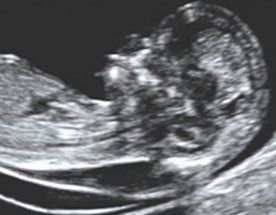

Si esegue a 11-14 settimane mediante ecografia.

La misurazione della Translucenza Nucale Fetale è stata introdotta dal 1992 presso il King's College di Hospital di Londra, per lo screening dei feti con anomalie cromosomiche. Attualmente la misurazione della Translucenza Nucale identifica più dell'80% dei feti affetti da trisomia 21 (Sindrome di Down) con il 5% di falsi positivi utilizzando come criterio un rischio di 1/300. L'enorme vantaggio della Translucenza Nucale, rispetto a tutti gli altri test, è che può identificare le gravidanze a rischio aumentato per altre malformazioni, soprattutto le cardiopatie fetali.

La Translucenza Nucale è quello spazio fluido che appare scuro all'esame ecografico, localizzato nella regione posteriore del collo. Se la quantità di fluido è maggiore della norma, il rischio di un'anomalia cromosomica o di una cardiopatia è aumentato. Viene utilizzato un programma computerizzato che combina lo spessore della Translucenza Nucale con l'epoca gestazionale (valutata con la misura della lunghezza fetale) e l'età materna, per calcolare il rischio di avere un feto con Sindrome di Down, di trisomia 13,trisomia 18 o di una cardiopatia. Se il rischio risulta maggiore di 1/300 si consiglia di eseguire una villocentesi oppure un'amniocentesi; comunque si consiglierà un'ecocardiografia ed un'ecografia morfologica a 20-22 settimane.

Giudizio: Molto interessante!! Semplice e precoce, ma necessita di un controllo di qualità! E' consigliabile che sia effettuato solo da operatori accreditati!